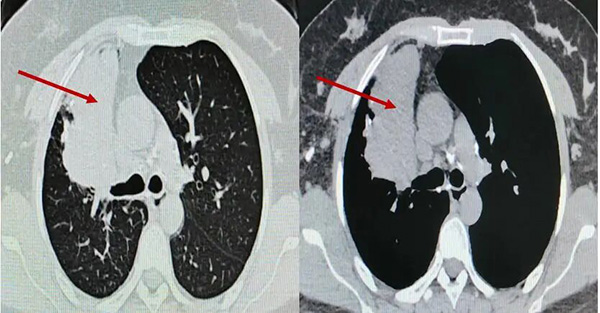

▲术前胸部CT

患者为36岁女性,既往有肺结核病史,近两年反复出现低热、咳嗽症状,胸部CT提示右肺上叶大片实变、坏死及多发黏液栓,气管镜显示支气管瘢痕性闭塞,化验提示曲霉菌感染。患者曾接受长期口服抗真菌药物治疗,但病灶未缩小,并出现视神经损害等药物并发症,停药后病情仍反复,右肺出现新发病灶。

经过系统治疗,患者低热症状消失,精神状态逐步好转。术后气管镜复查显示右上叶前段闭塞支气管已重新开放,坏死物基本清除;胸部CT显示原新发病灶消失,前段病灶引流通畅,炎症吸收良好,成功保留了右肺功能。